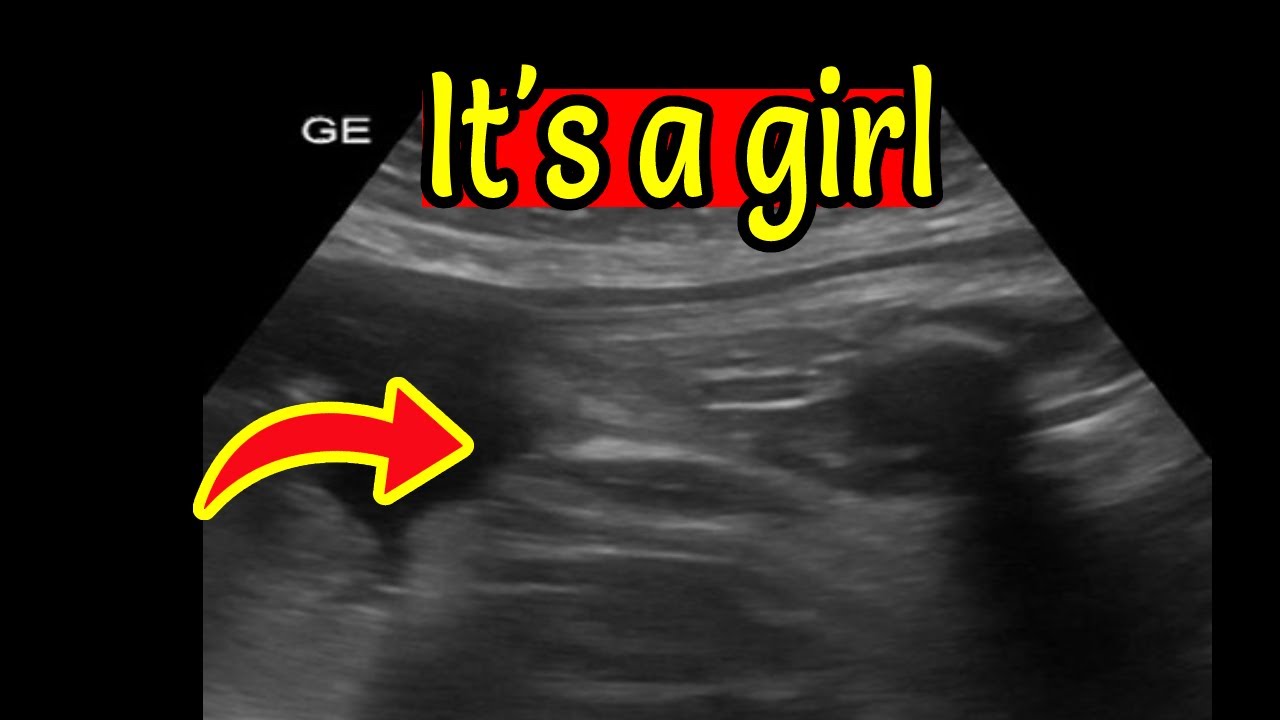

It s Baby Boys Day Gender Compilations Various Weeks Ultrasound

How To Know Baby Boy Or Girl In Ultrasound Report part A Aqsa

How To Know Baby Gender On Ultrasound Report Urdu Hindi Ultrasound Se